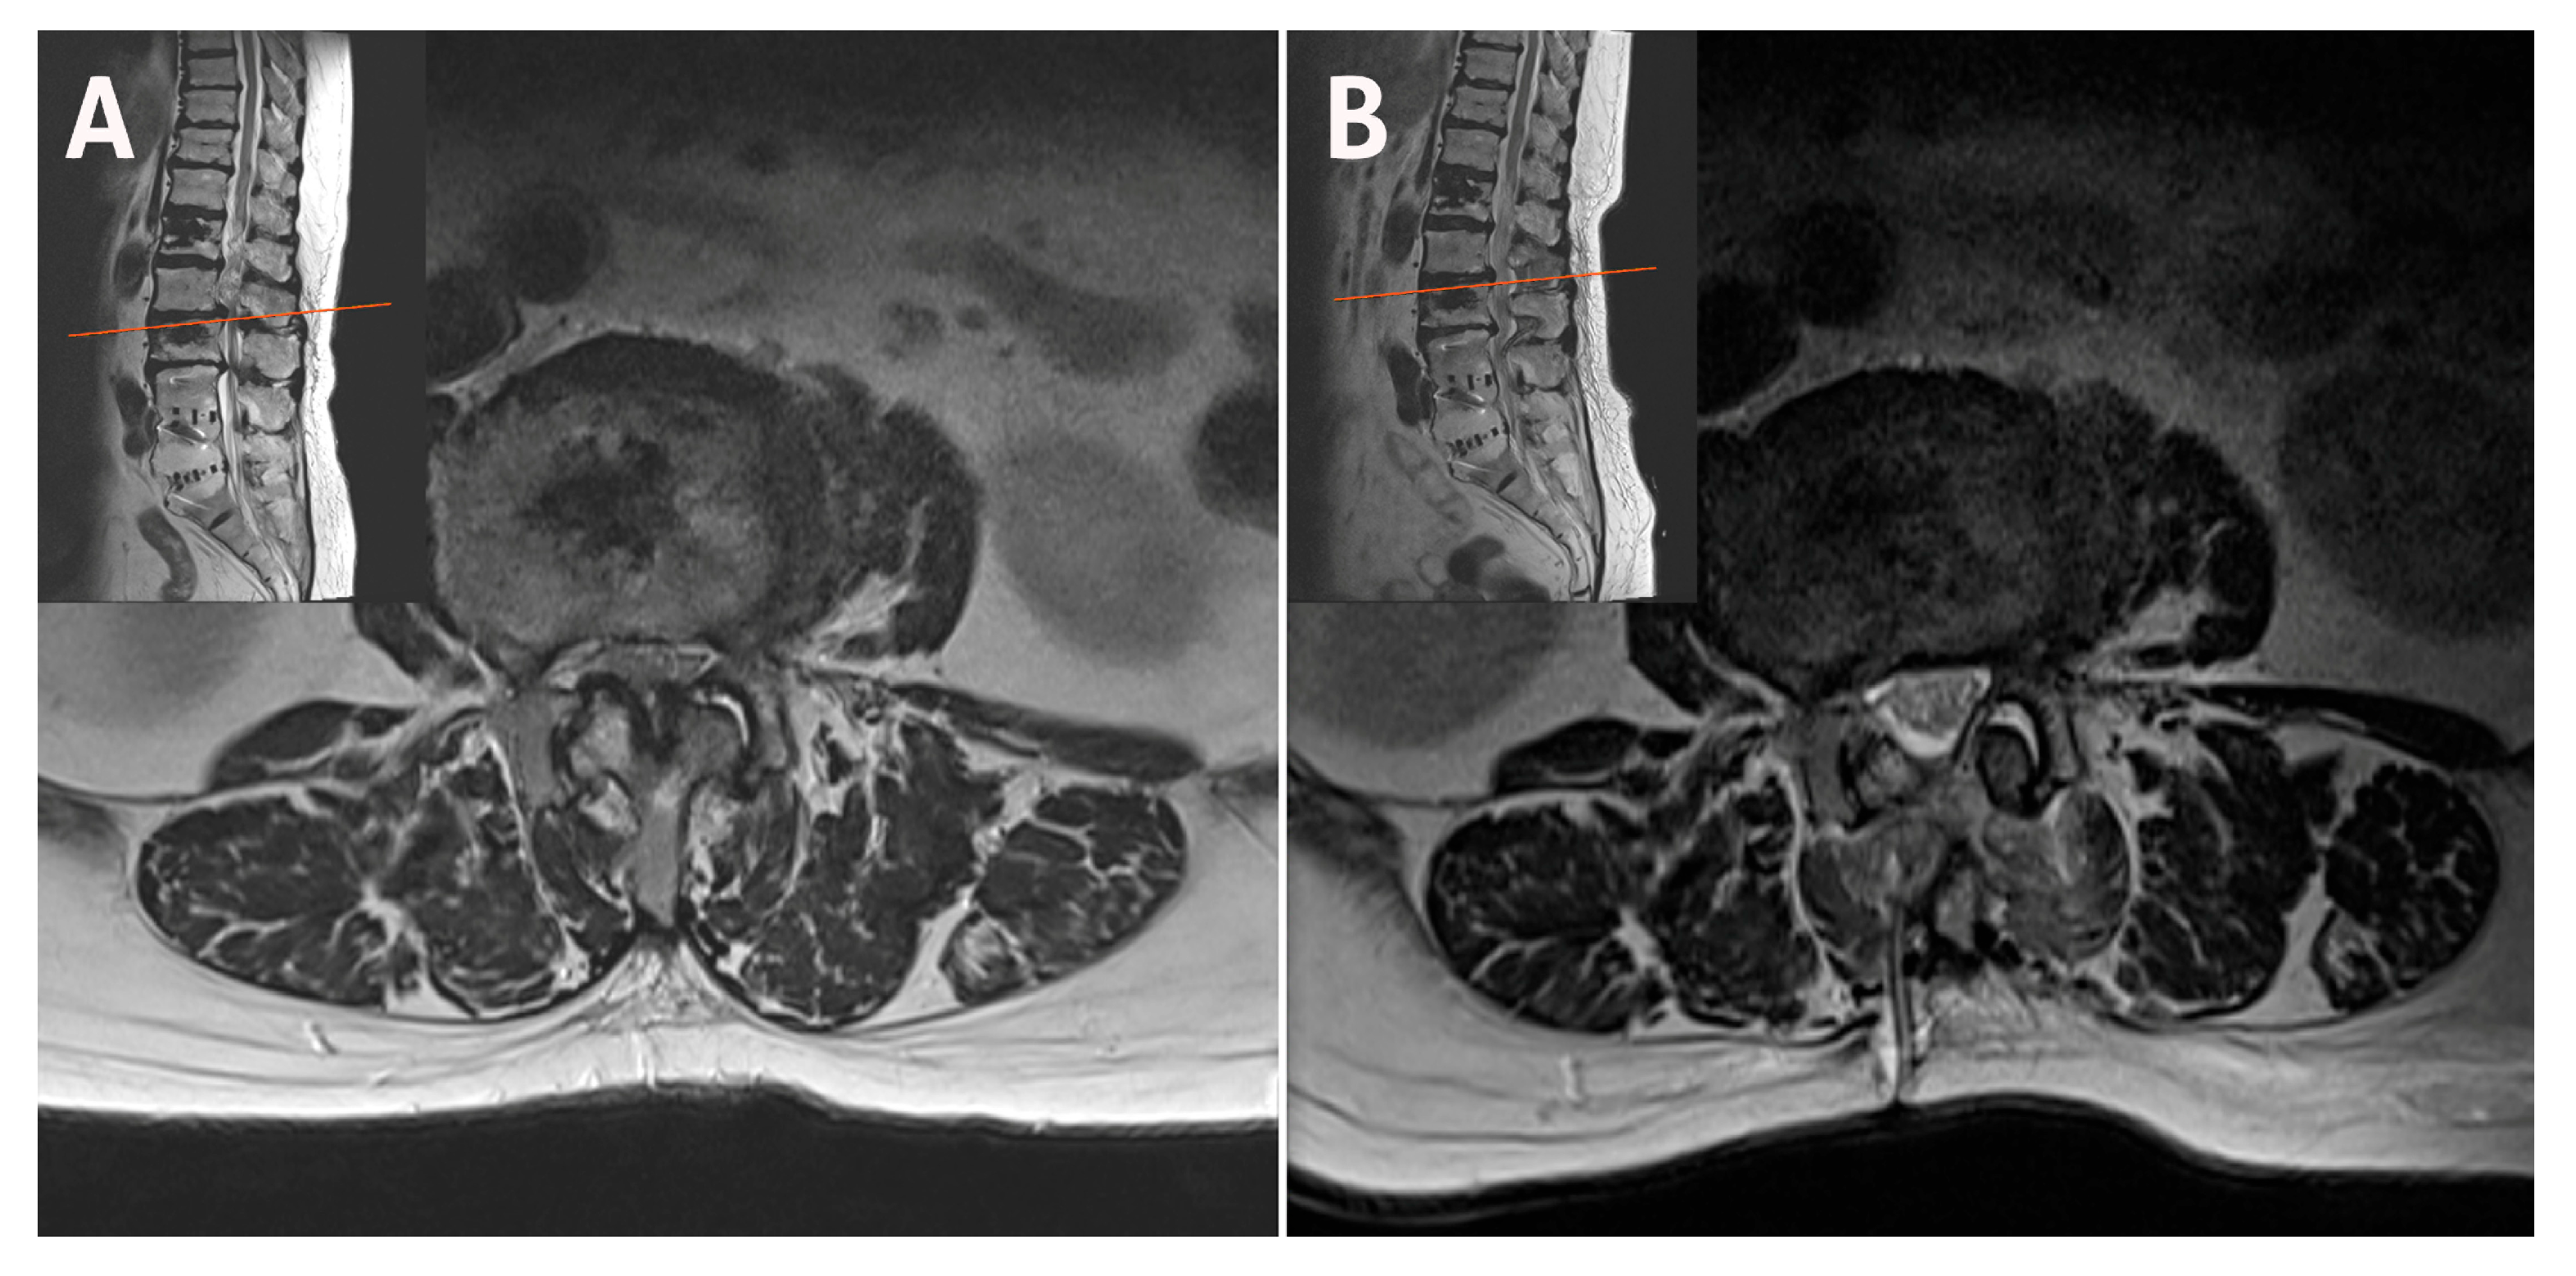

2.2. Case 2: Bilateral–Contralateral Decompression in Adjacent Segmental Stenosis (ASS) After Lumbar Fusion